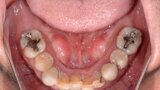

Fig. 3: Pre-op mandibular occlusal view.